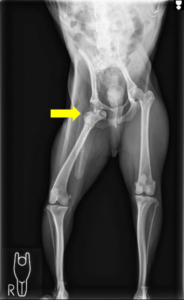

レントゲン検査にて、右の股関節が完全に脱臼していることを確認しました。

飼い主様とご相談の結果、関節を温存し、根本的に安定させることを目指して、トグルピン法による外科手術を実施しました。